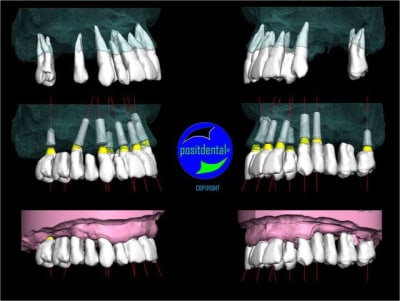

gestion des artéfacts en présence de couronnes

Wax up 3d positdental 8 kt8qmy - Eugenol

Wax up 3d positdental 9 c7cv9z - Eugenol